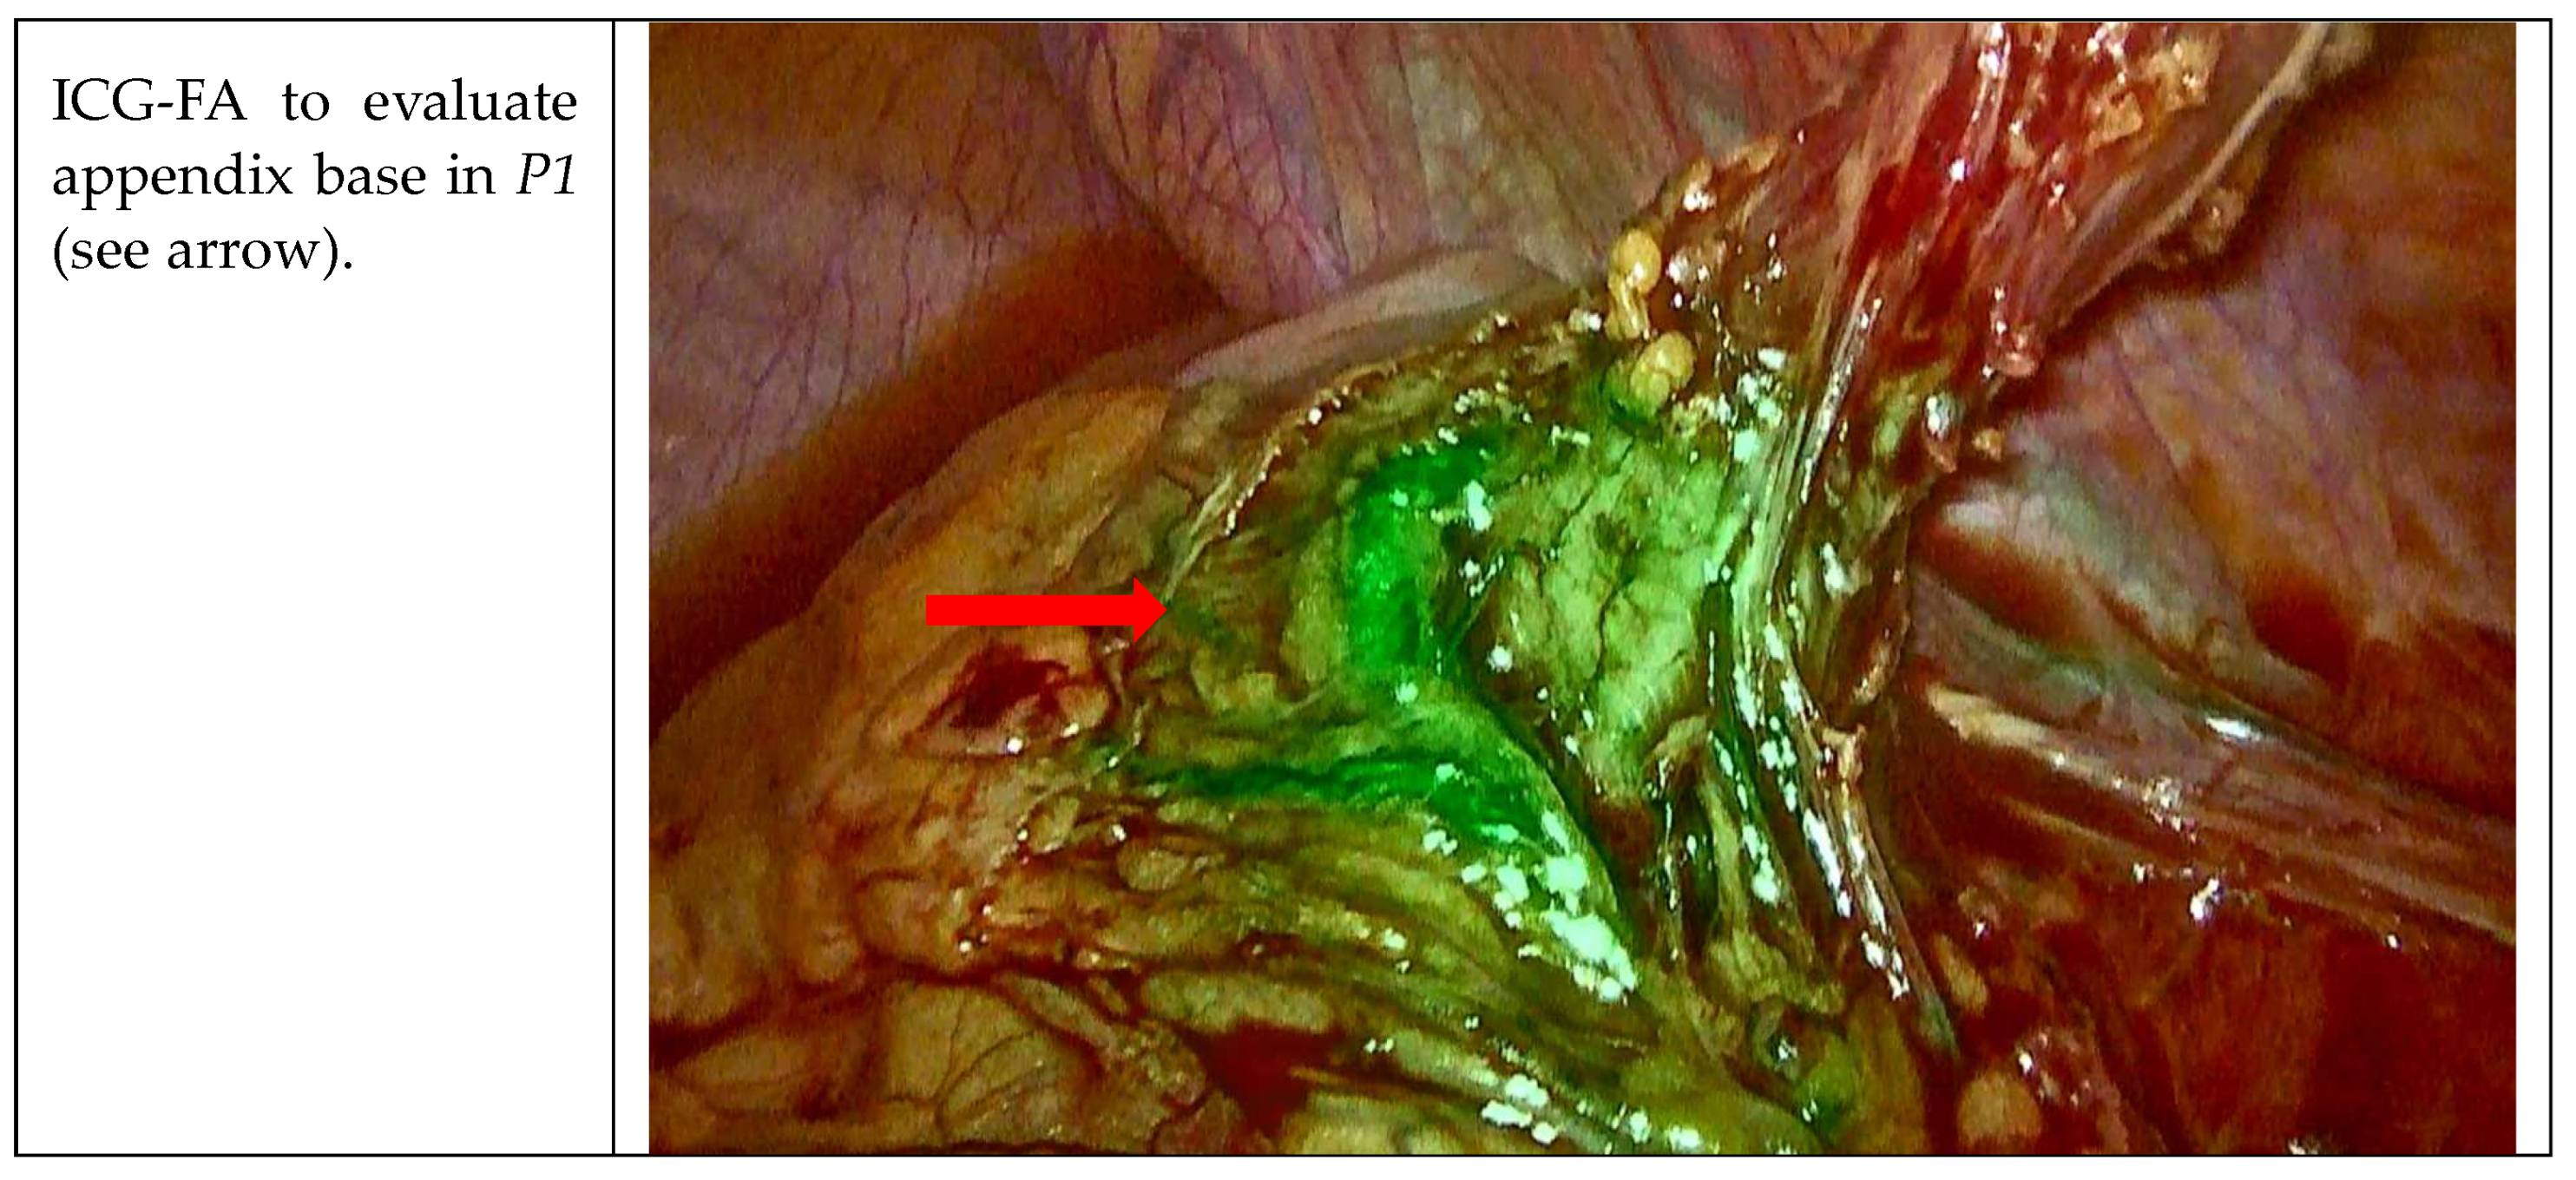

| P1 | M | 20 years | 24.7 | WBC 17.14 109/L, CRP 0.08 mg/dL | No | Caucasian |